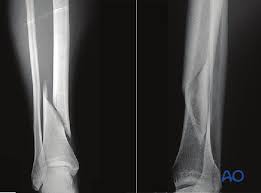

Spiral fractures are complete fractures of long bones that result from a rotational force applied to the bone. Summary summary (text) medline pmcid list. Spiral fractures are usually the result of high energy trauma and are likely to be associated with. Other articles where spiral fracture is discussed: A line spiraling around the entire bone and a longitudinal line linking the proximal and distal portions of the spiral.

Spiral fractures are usually the result of high energy trauma and are likely to be associated with. Summary summary (text) medline pmcid list. A fracture, sometimes called a torsion fracture, in which a bone has been twisted apart. Spiral fractures often occur when the body is in motion while one extremity is planted. Spiral fracture — sagittarius a star 03:25. Detailed step by step desription of intramedullary nailing for simple fracture, spiral located in our module intramedullary fixation is valuable and appropriate for the majority of tibial fractures. Two spiral fractures sustained following only minor trauma. Meaning of spiral fracture medical term.

Two spiral fractures sustained following only minor trauma. Complete fractures are categorized based on the way the bone breaks. It occurs due to a rotational, or twisting, force. Try our newest study sets that focus on spiral fracture to increase your studying efficiency and retention. Detailed step by step desription of intramedullary nailing for simple fracture, spiral located in our module intramedullary fixation is valuable and appropriate for the majority of tibial fractures. Other articles where spiral fracture is discussed: A spiral fracture is a bone fracture occurring when torque is applied along the axis of a bone.1 spiral fractures often occur when the body is in motion while one extremity is planted. Spiral fracture femur (there is a significantly displaced spiral fracture of the proximal femoral. A spiral fracture, also known as torsion fracture, is a type of complete fracture. A spiral fracture is a bone fracture caused by a twisting force. A spiral fracture is usually treated right away with surgery. Summary summary (text) medline pmcid list. Know ways to lower your risks in the first place.

Spiral fracture femur (there is a significantly displaced spiral fracture of the proximal femoral. A spiral fracture is usually treated right away with surgery. Summary summary (text) medline pmcid list. A spiral fracture is a bone fracture that occurs when a long bone is broken by a twisting force. Also called a torsion fracture, a spiral my son suffered a spiral femur fracture and the er doctor didn't report it. It occurs due to a rotational, or twisting, force. Detailed step by step desription of intramedullary nailing for simple fracture, spiral located in our module intramedullary fixation is valuable and appropriate for the majority of tibial fractures. Medical definition of spiral fracture. Spiral fractures are complete fractures of long bones that result from a rotational force applied to the figure 1. Spiral fractures are usually the result of high energy trauma and are likely to be associated with. Try our newest study sets that focus on spiral fracture to increase your studying efficiency and retention. Bone depressed fracture fractures simple fracture closed reduction. Finally, two days later, the other.